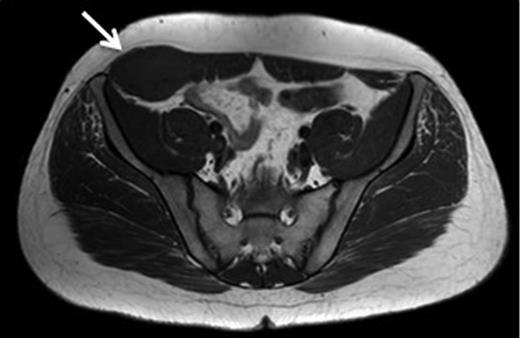

A 43-year-old Caucasian female presented to her General Practitioner in April 2012 with a 2-year history of a firm, painful swelling in the right flank. MRI revealed a 5.0 × 6.0 × 7.0 cm enhancing lesion with areas of necrosis, which was invading the antero-lateral abdominal wall (Fig. 1 ). With radiological features highly suggestive of a sarcoma, she underwent an ultrasound-guided biopsy, which classified the mass as a borderline myoepithelial tumour. The patient underwent an uncomplicated resection of the mass, which left a 10 × 10 cm right-sided antero-lateral abdominal wall defect. The defect was repaired using a Biodesign® biological graft. Initially, a layer of the biological mesh was used to cover the intact peritoneum with attachments cranially to the ribs and inferiorly to the right iliac crest. The external oblique was mobilized to partially cover the mesh, and a further layer of the biological mesh attached over it with Ethilon™ (Fig. 2). The patient had an uncomplicated postoperative recovery. The tumour histology revealed a 6.5 × 6.0 × 5.5 cm myxoid mass; immunohistochemistry analysis favoured a benign/borderline myofibroblastic tumour. At 24-month follow-up, she had good wound healing with a small area of paraesthesia inferior to the scar. An MRI showed good graft incorporation and no evidence of disease recurrence or hernia (Fig. 3).

T1 MRI showing a soft tissue abdominal wall tumour involving external oblique, internal oblique and transversus abdominis and not involving the peritoneum (arrow).